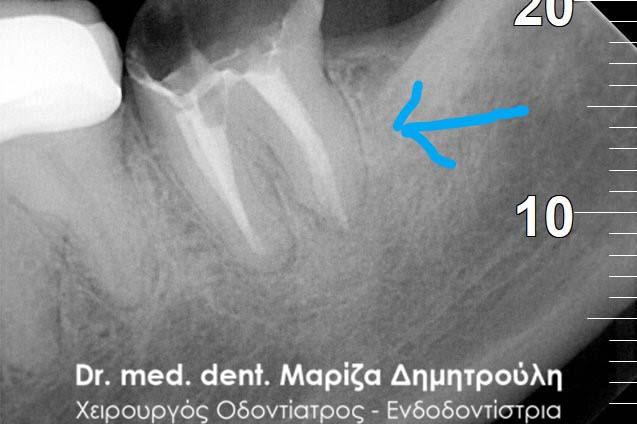

Μετά από τη χορήγηση τοπικής αναισθησίας και την τοποθέτηση ελαστικού απομονωτήρα ακολούθησε η διάνοιξη του δοντιού. Αμέσως μετά την αφαίρεση του προσωρινού σφραγίσματος παρατηρήθηκε έντονη και απότομη αιμορραγία του δοντιού, η οποία προερχόταν από ένα συγκεκριμένο σημείο. Η κλινική αυτή εικόνα επιβεβαίωσε τις υποψίες για διάτρηση του δοντιού. Εντοπίστηκε το σημείο της διάτρησης και έγινε έλεγχος με μία ακτινογραφία. Στη συνέχεια πραγματοποιήθηκε η αποκατάσταση της διάτρησης με ειδικό υλικό και εντοπίστηκε ο τρίτος σωλήνας του δοντιού. Η όλη διαδικασία επιβεβαιώθηκε με τη λήψη ακτινογραφίας.

Εντοπισμός του τρίτου ριζικού σωλήνα